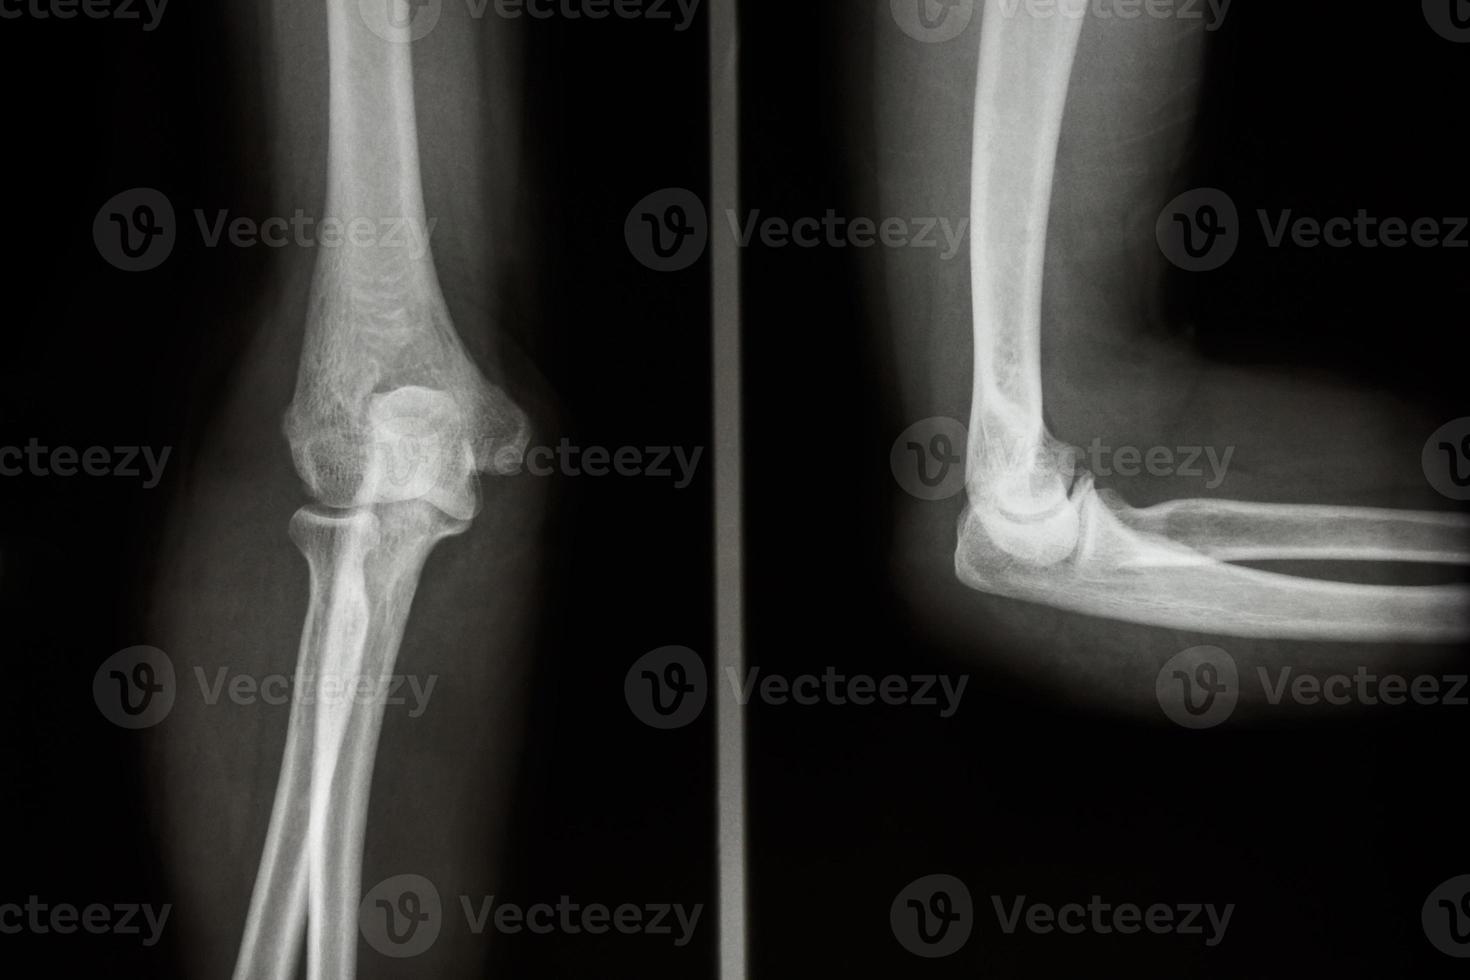

From www.vecteezy.com

film xray elbow AP and Lateral view show normal human s elbow 2493647 What Does An Elbow X Ray Show  A routine radiographic evaluation of the elbow includes an anteroposterior (ap) and true lateral view. Anteroposterior (ap) and lateral radiographs remain the workhorses of elbow imaging. Check the anterior humeral line: On the lateral radiograph, inspect for the displacement of the anterior and posterior fat pads embedded in the. The elbow series is a set of radiographs taken to investigate. What Does An Elbow X Ray Show.